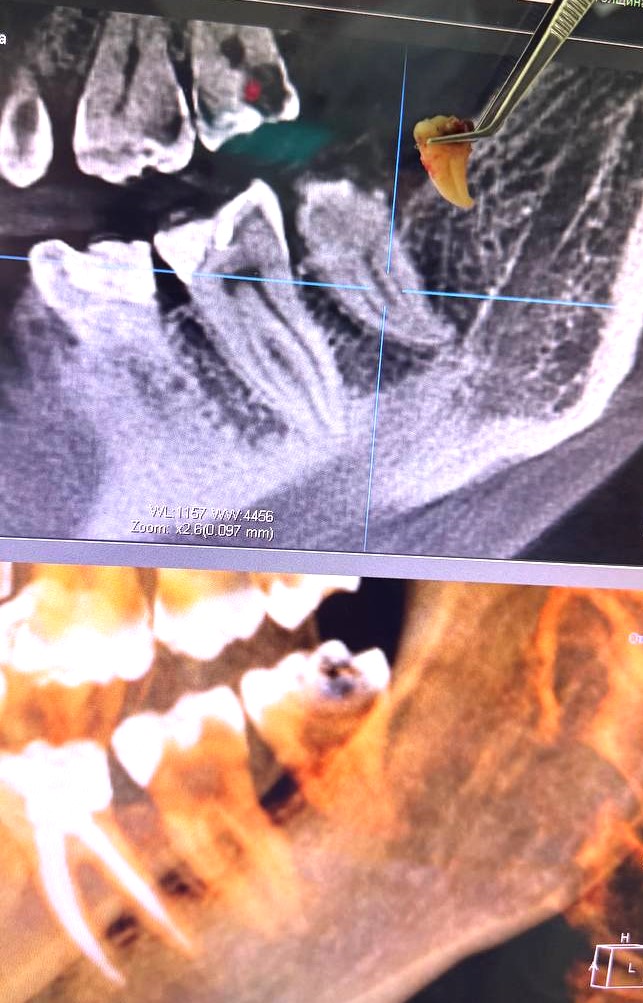

Атравматичное удаление зубов – наиболее безболезненная и щадящая процедура, которая практически не травмирует десну и костную ткань.

Зуб извлекается частями, что позволяет не травмировать окружающие ткани.

В нашей клинике осуществляется удаление самых сложных «зубов мудрости». Обычно удаление зуба под местной анестезией занимает от 10-15 минут, но иногда процедура может занять 30 или даже 60 минут и более.